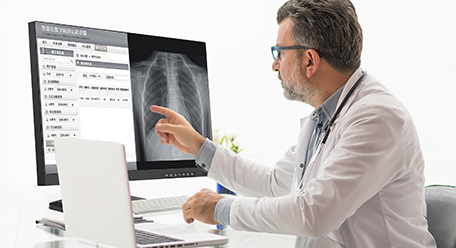

Moniteur de radiologie diagnostique

Moniteur de radiologie diagnostique

Application fields: Radiography room/film reading room/ radioautography workstation/imaging equipment.